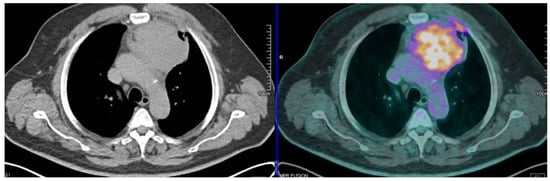

2.1. PET/CT to Distinguish Thymic Hiperplasia from Thymic Epithelial Tumours

18F-FDG PET May Be Useful to Distinguish Thymic Hiperplasia from Thymic Epithelial Tumours Is Integrated with Anatomical Consideration and Spatial 18F-FDG Uptake Distribution